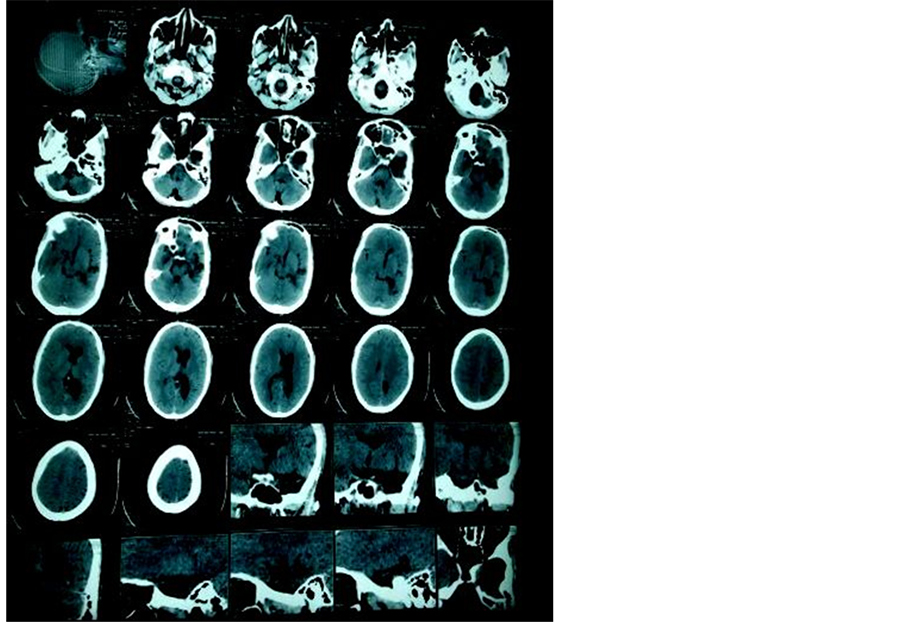

The CT Brain was suggestive of left sided cerebral hemiatrophy with epsilateral enlargement of lateral ventricle (Ventriculomegaly); features suggestive of Dyke Davidhoff Masson Syndrome (DDMS) (See Figure 1 & Figure 2). MRI brain with MR angiography was done to confirm the diagnosis and delineate the arterial system after stabilization.

Figure 1. CT scan Brain showing cerebral hemiatrophy with unilateral (Left) ventriculomegaly.